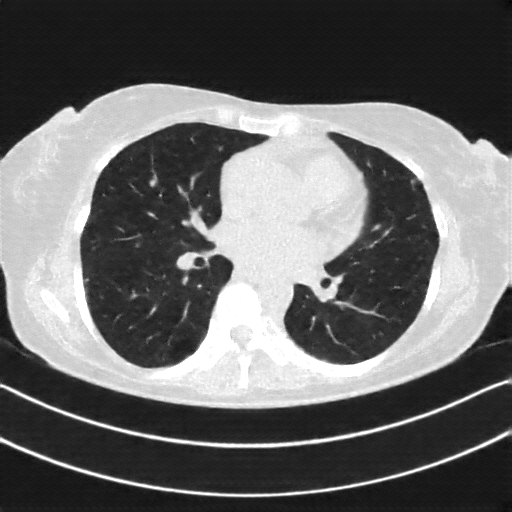

Reconstructed NATIVE CT scan (cycle consistency)

Full window (WL 1023.5, WW 4095 β†’ Low βˆ’1024, High +3071)

Actual HU range: [-1024.0, 1627.2]

Lung window (WL -600, WW 1500 β†’ Low βˆ’1350, High +150)

Actual HU range: [-1120.3, 150.0]

Mediastinum window (WL 40, WW 400 β†’ Low βˆ’160, High +240)

Actual HU range: [-160.0, 240.0]